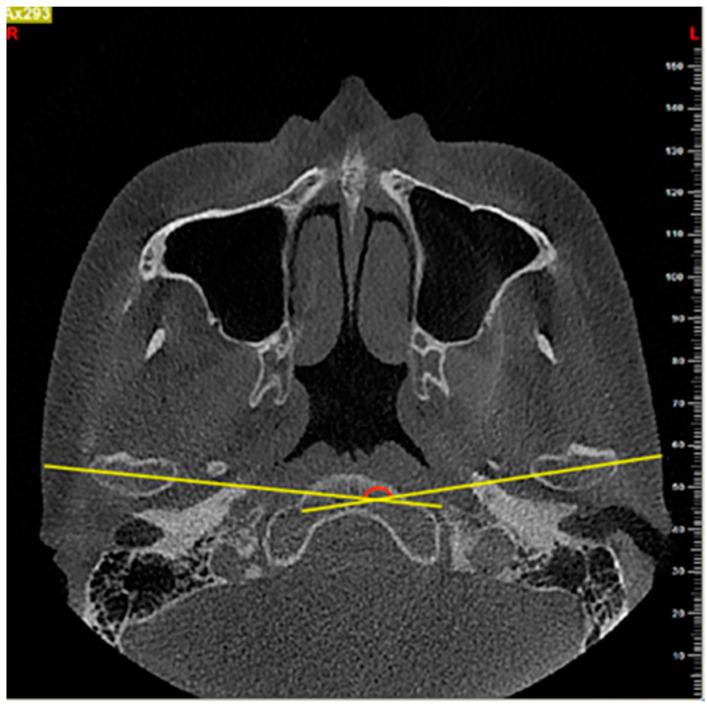

(1) Background-The aim of the present study was to evaluate the correlation between the temporomandibular joint (TMJ) osseous morphology of normal skeletal pattern individuals with different dental malocclusions by using cone-beam computed tomography (CBCT). (2) Methods-The CBCT images of bilateral TMJs in 67 subjects with skeletal class I and average mandibular angle (26 males and 41 females, age range 20-49 years) were evaluated in this study. The subjects were divided into class I, class II division 1, and class II division 2 according to the molar relationship and retroclination of the maxillary incisors. Angular and linear measurements of TMJ were evaluated and the differences between the groups were statistically analyzed. (3) Results-Intragroup comparisons showed statistical differences for articular eminence inclination, the width of the glenoid fossa, the ratio of the width of the glenoid fossa to the depth of the glenoid fossa, the condylar angle, and the intercondylar angle between the malocclusion groups. The measurements of the glenoid fossa shape showed no significant difference between the left and right sides. Females showed more differences in the morphological parameters of TMJ between the three malocclusion groups than the males. (4) Conclusion-The present study revealed differences in the TMJ osseous morphology between dental class I and class II malocclusions in the normal skeletal pattern.